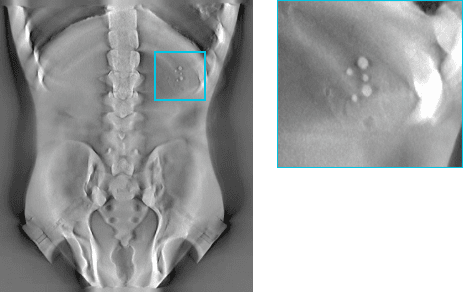

Knee / Weight bearing - Human knee

Chest - Lungman Phantom

Before

After

4343 + Linear Motion: Lungman

4360(대면적): Lungman